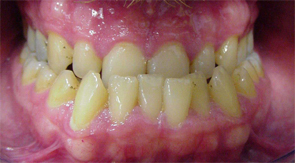

Zahnfehlstellung Engstand

Engstand nennt sich der Platzmangel der Zähne bei

einem zu kleinen Kiefer [6]. Kiefer werden zu klein

-- durch zu wenig Wachstumsreiz, wenn das Kind nicht

gestillt wird, sondern immer die Flasche bekommt [2]

-- durch Verlust der Milchzähne im frühen Kindesalter

durch Flaschenkaries, so dass die Milchzähne ihre

Rolle als "Platzhalter"nicht mehr wahrnehmen können

[5].

Engstand der Zähne, eine Frontalansicht |

Engstand bei einem Unterkiefer, eine Sicht

von oben (mit Sicht auf die Oberflächen,

lat. Facies [7]) |